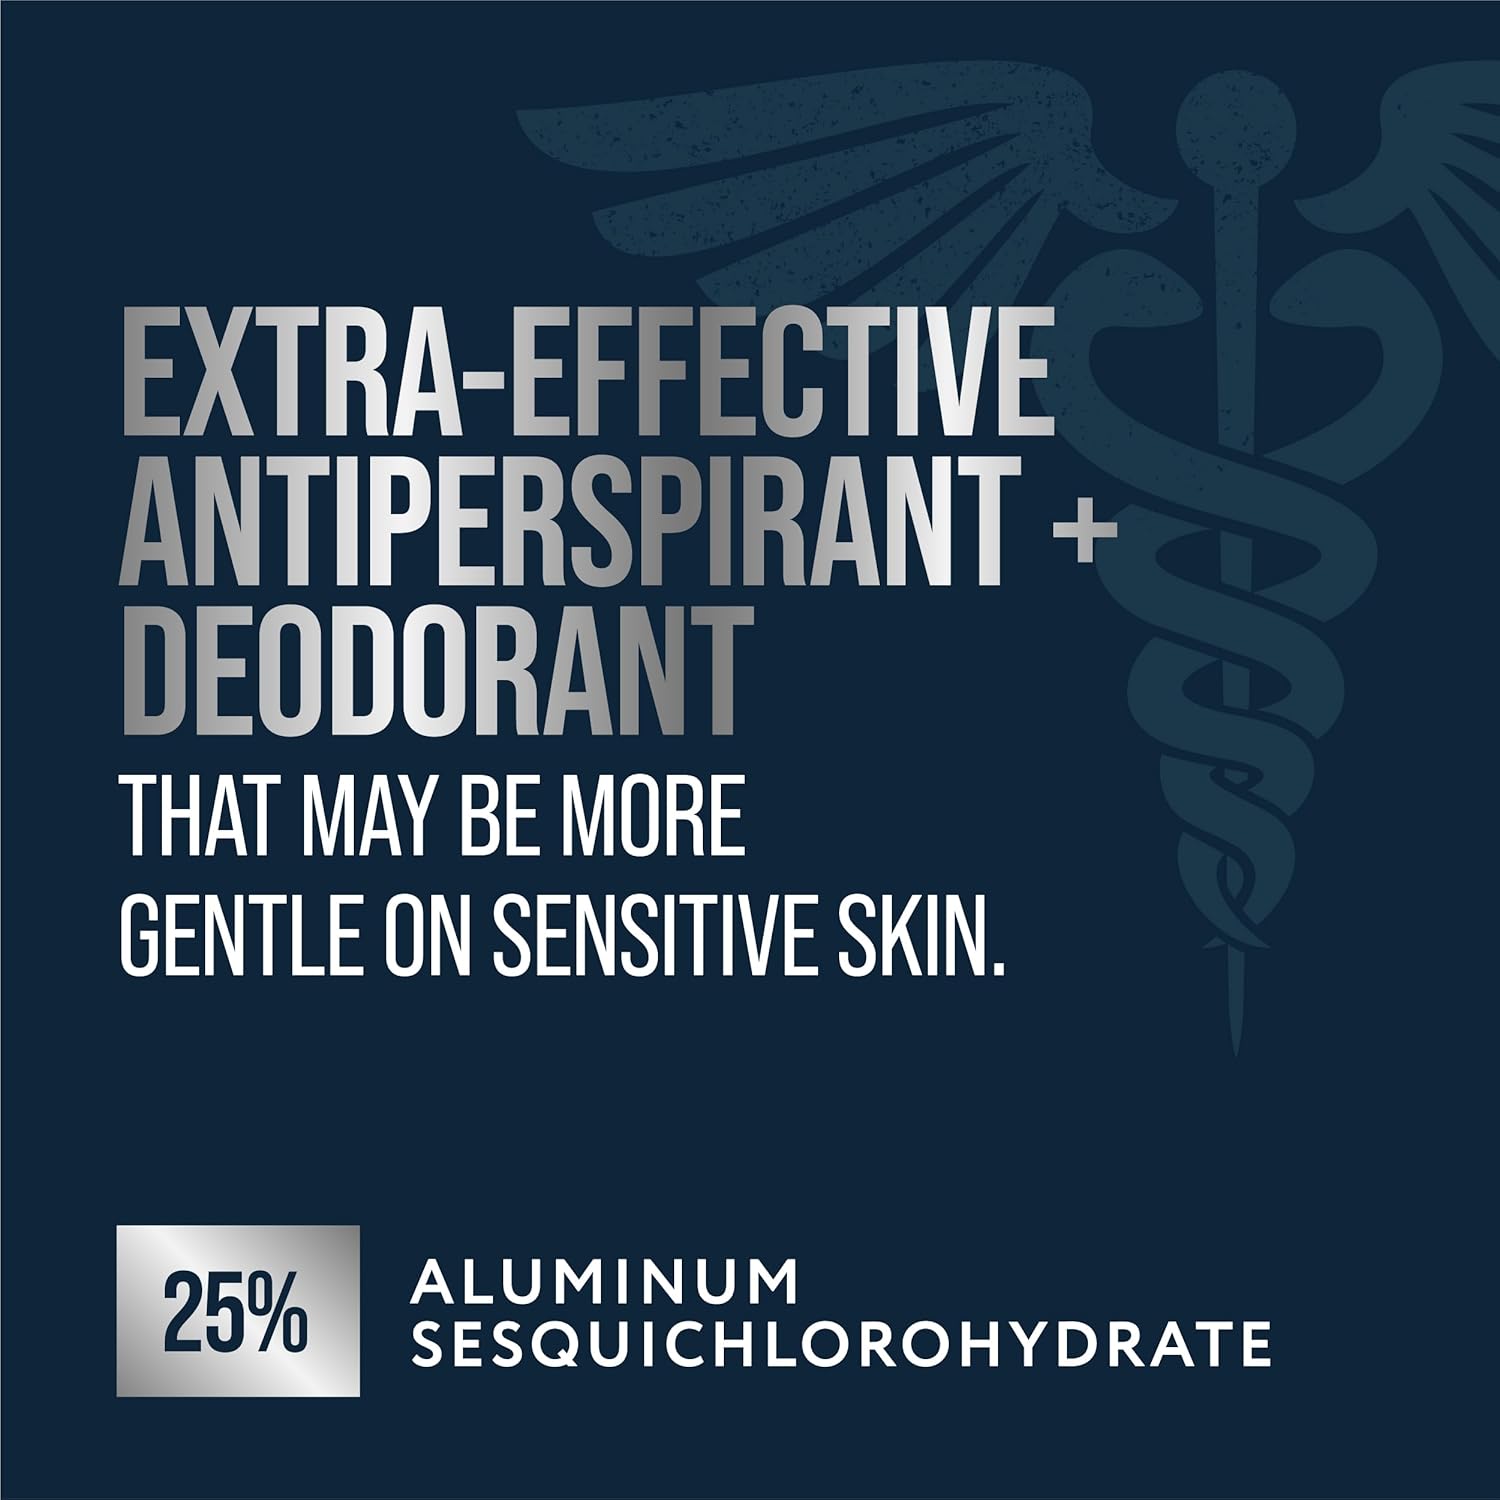

- CLINICAL STRENGTH PROTECTION: Extra-effective formula designed specifically for Hyperhidrosis and excessive sweating.

Regain your confidence with Certain Dri Extra Strength Clinical Solid Antiperspirant, the #1 doctor-recommended brand for excessive sweating. Specially formulated for Hyperhidrosis, this clinical-strength solid utilizes Aluminum Sesquichlorohydrate to deliver up to 72 hours of reliable sweat and odor protection. Unlike standard deodorants that merely mask wetness, Certain Dri targets the source of perspiration to keep you dry day and night. The gentle formula is designed to be applied sparingly at bedtime to completely dry skin, allowing the active ingredients to work while you sleep for maximum effectiveness. Wake up feeling protected and fresh, without the worry of sweat stains or body odor. This pack contains one 1.7 oz stick in a Powder Fresh scent.